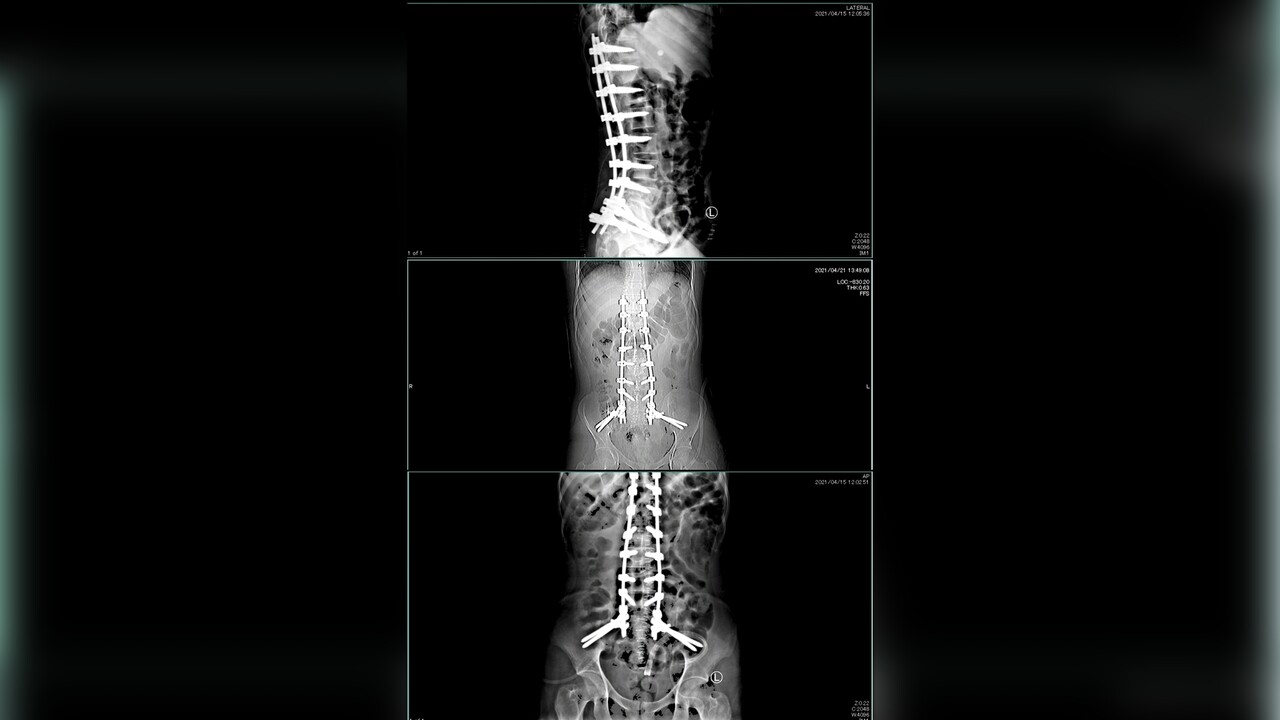

In the year 2021, my life took an unexpected and tragic turn when I was involved in a serious accident while I was traveling in Thailand. This incident resulted in catastrophic injuries, including a broken spine and a ruptured bladder. Several extensive surgeries became a critical part of my journey towards recovery, and now, as I navigate the aftermath, I find myself facing the harsh reality of living with chronic back pain, severely limited mobility, and a multitude of challenges that affect every aspect of my life.